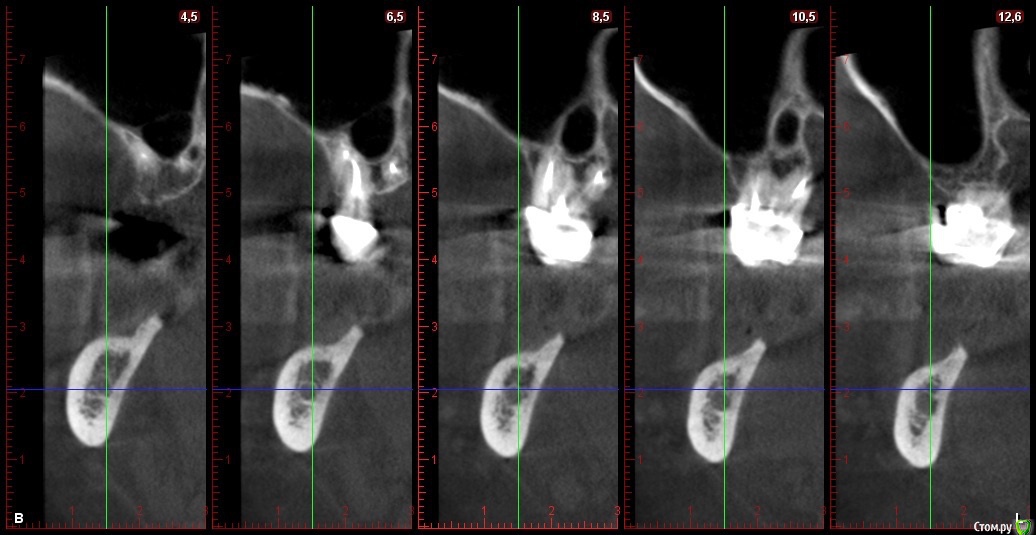

Глеб Митрофанов Опубликовано 22 октября, 2015 Автор Поделиться Опубликовано 22 октября, 2015 Срезы кт Ссылка на комментарий

basha.ru Опубликовано 23 октября, 2015 Поделиться Опубликовано 23 октября, 2015 Спасибо за кейс.Скажите пожалуйста какая высота кости до нижнечелюстного канала?Спасибо. Ссылка на комментарий

Глеб Митрофанов Опубликовано 23 октября, 2015 Автор Поделиться Опубликовано 23 октября, 2015 (изменено) Спасибо за кейс.Скажите пожалуйста какая высота кости до нижнечелюстного канала?Спасибо.До канала , в самой низшей точке - 4,5-5 мм Изменено 23 октября, 2015 пользователем Глеб Митрофанов Ссылка на комментарий